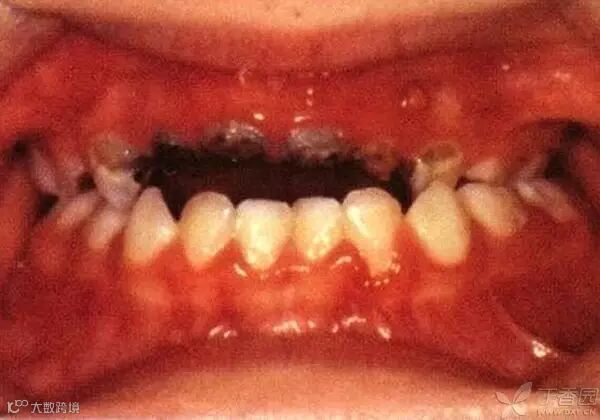

3、龋齿进化记

早期,牙齿表面出现白斑或脱矿带;

中期,牙齿病情向周围蔓延,脱矿带颜色变深,侵蚀邻居牙齿形成棕色龋面;

终期,易发生牙冠折断,严重者只留下残根。

PS 龋齿形成期间,随着病情的加重,婴幼儿可能会感到牙齿剧烈疼痛、牙龈肿胀、流脓,出现牙髓炎、牙周脓肿等并发症。

没错,这就是儿童龋齿的养成过程,丝毫没有夸张,因为小药经常听口腔科朋友诉说接待严重龋齿小患者时玻璃心碎满地的痛楚。不信?拿来朋友的手机给你们看!